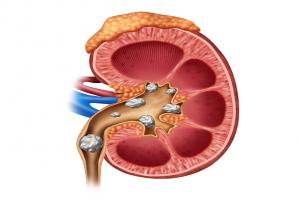

Body part(s) involved-

Esophagus

Stomach

Intestine